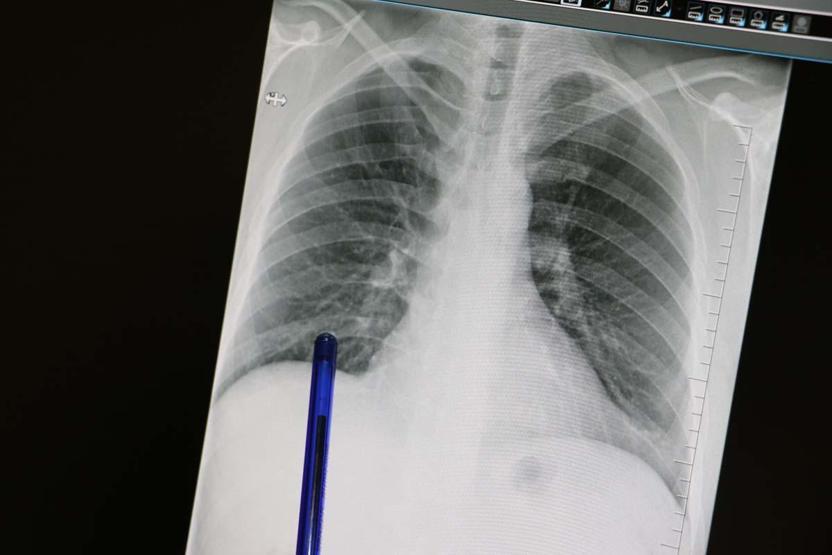

Akciğer kanserinin büyük bir kısmını sigara ile ilişkili olduğunu söyleyen Büşra Yayla Yerlikaya, "Bu hastalık, hem dünyada hem de ülkemizde kansere bağlı ölümlerin en sık nedenidir. Ne yazık ki genellikle erken evrede belirti vermediği için geç tanı alabilmekte ve bu da tedavi şansının azalmasına sebep olabilmektedir.

Akciğer kanserlerinin büyük kısmı, neredeyse yüzde 85-90 kadarı bilindiği üzere sigarayla ilişkilidir. Günde içilen sigara sayısı ve kullanım süresi arttıkça risk de katlanarak artar. Ancak hiç sigara içmeyenlerde de pasif içicilik de en az aktif içicilik kadar önemli bir faktördür. Elektronik sigaralar ya da ısıtılmış tütün ürünleri de sanıldığı gibi güvenli değildir. Nikotin içerdikleri için bağımlılığı sürdürürler ve ekstra pek çok kimyasal daha içerirler. Uzun vadeli zararları henüz tam olarak bilinmemektedir" dedi.